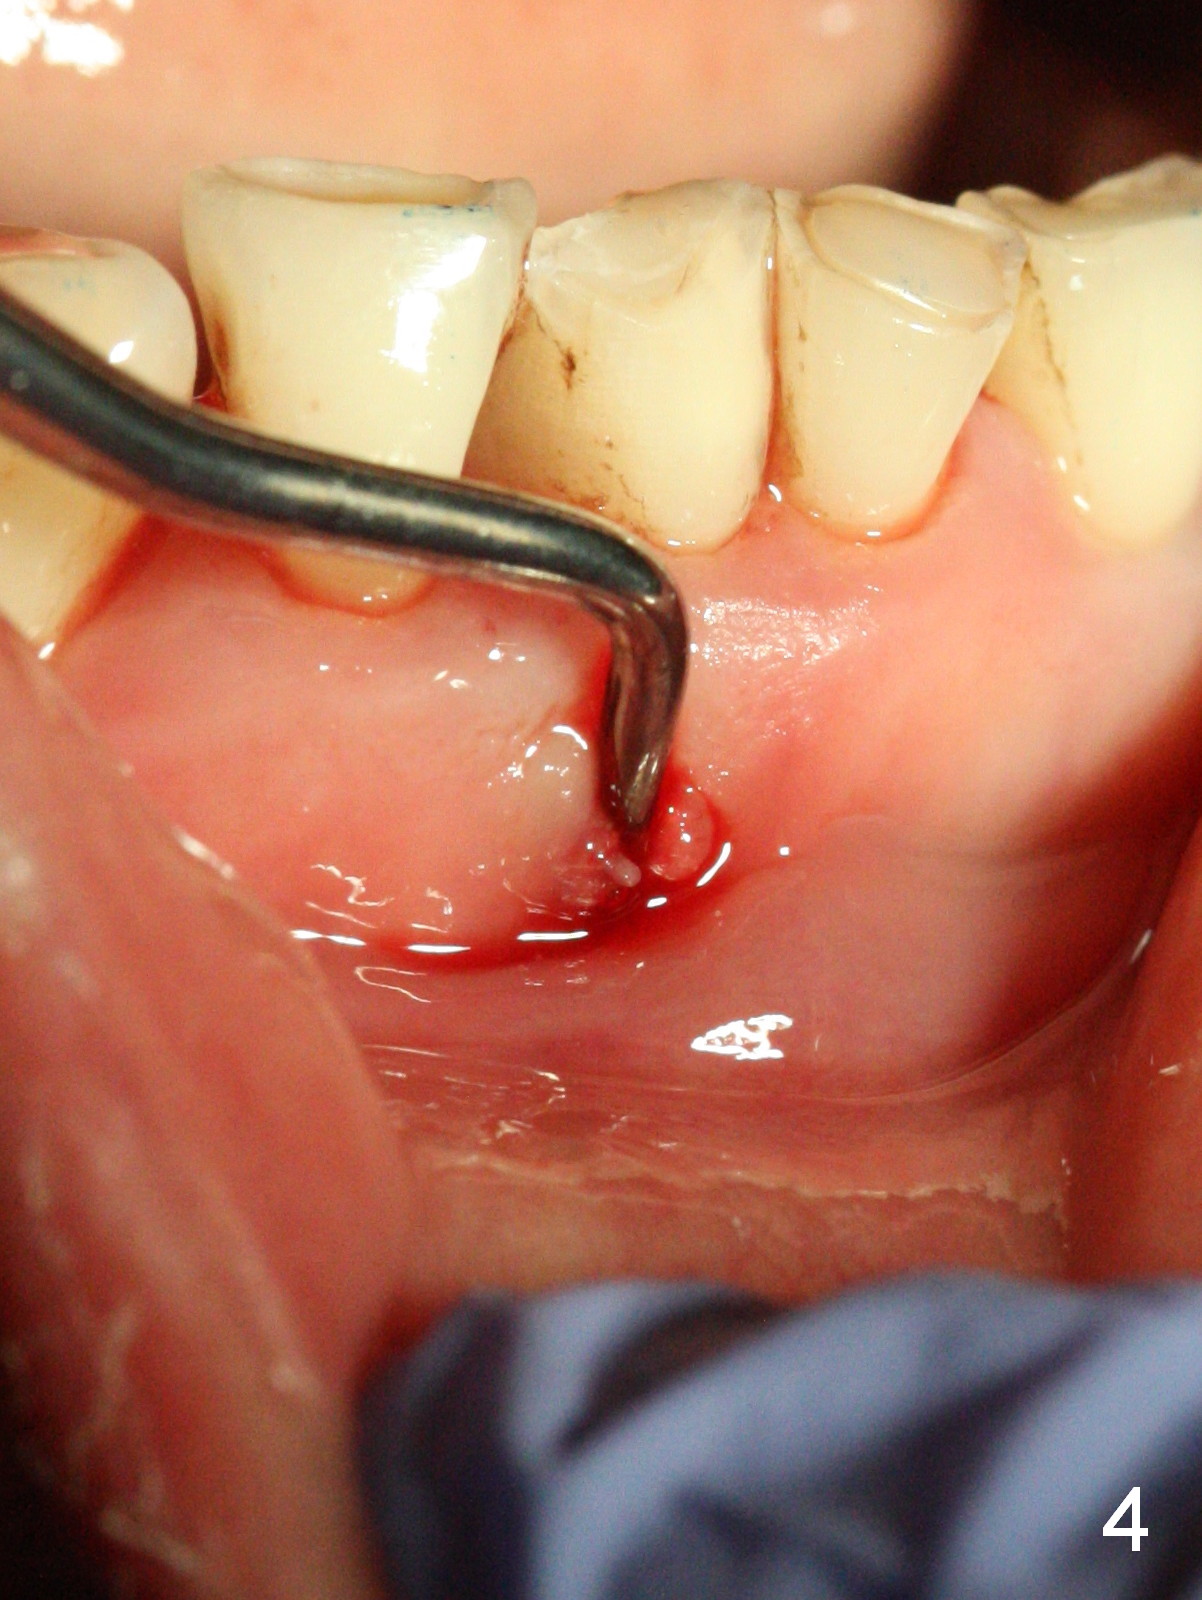

A 45-year-old man has had a chronic fistula associated with the tooth #25 (Fig.1). There is purulent discharge sometimes. After debridement with hand files #10-20 and rotary one 30/06, a master cone 30/.06 is inserted incompletely (Fig.2). After rotary files 30/.08 at 16.0 mm and 30/.10 at 15.0 mm and hand files 10-20 at 17 mm, the master cone is apparently inserted to the WL. With application of Endo Sequence Sealer (syringe), the master cone is reinserted (Fig.3). When the rubber dam is removed, the sealer is found to have expelled from the fistula. With an endo curette (Fig.5), the sealer is removed from the deepest portion of the sinus tract (apex of the tooth). What do you want to know the outcome of the supplementary surgical maneuver? The sealer is gone (Fig.6). The immediately supplementary treatment avoids a separate apicoectomy. No fistula is noted <2 weeks postop (Fig.7). The attrition is due to #8 and 9 veneers, fabricated 8 years earlier. The tooth #24 is symptomatic with loss of incisal composite nearly 4 years postop (Fig.8 <). After 30/.04 gutta percha (GP) try in (Fig.9), RCT is finished without accessory GP (Fig.10).